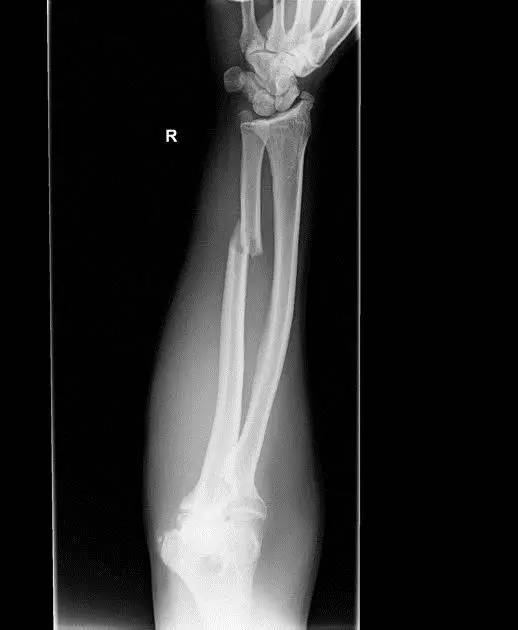

(3)Holstein lewis 骨折

肱骨远端 1/3 骨折伴桡神经嵌压。